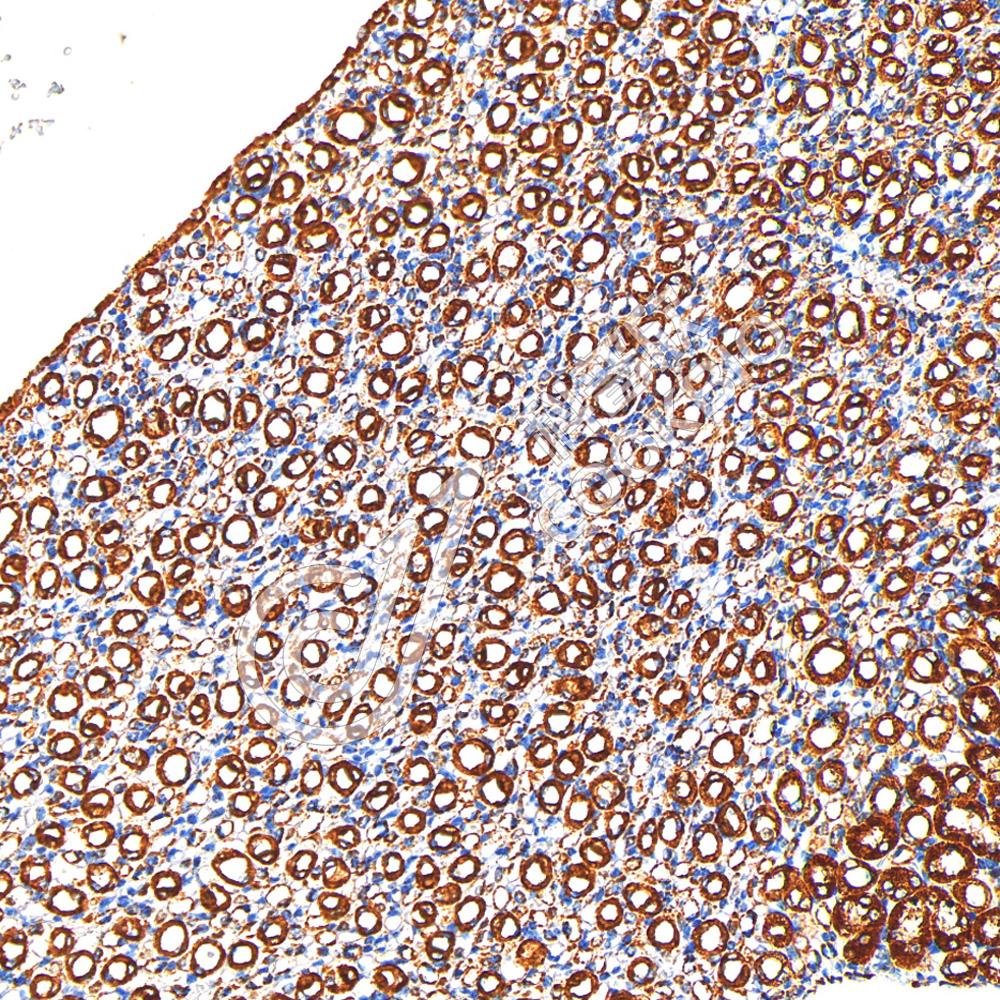

IHC检测COX IV蛋白(货号 K5450039).

样品: 大鼠肾, 4%多聚甲醛 (货号KSG1101) 固定12-24小时.

抗原修复: 柠檬酸抗原修复液(干粉, pH 6.0) (KSG1201), 高压锅均匀喷气计时2分钟.

—抗: 1: 600稀释, 4℃ 孵育过夜.

二抗: S-vision免疫组化多聚二抗(山羊抗兔),即用型 (货号KB3906), 室温孵育20分钟.

样品: 小鼠肾, 4%多聚甲醛 (货号KSG1101) 固定12-24小时.